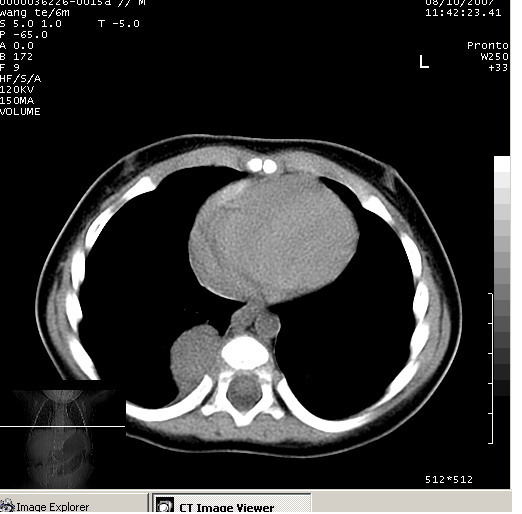

患儿男、6个月,因咳嗽三天曾拍胸片考虑肺部感染,这是在胸片后约一周左右作的ct。

右下肺纵隔旁软组织密度影,边界清楚,内见点状高密度影。支持考虑:神经源性肿瘤!

右下肺纵隔旁软组织密度影,宽基底紧贴胸椎与肋骨,边界清楚,内见点状高密度影。支持考虑:神经源性肿瘤!肺隔离症待排

右下肺纵隔旁软组织密度影,边界清楚,考虑神经源性肿瘤。

右下肺纵隔旁边界清楚软组织密度影,内见点状高密度影。考虑:神经源性肿瘤!

同意神经源性肿瘤的诊断,如果患儿一般情况不差的话,神经节细胞瘤可能性要大一些,隔离肺的可能性小,如果考虑叶内型隔离肺,孩子平时感染的机会可能比较多,增强后可排除

典型的神经源性肿瘤

支持神经源性肿瘤,有肋骨破坏。